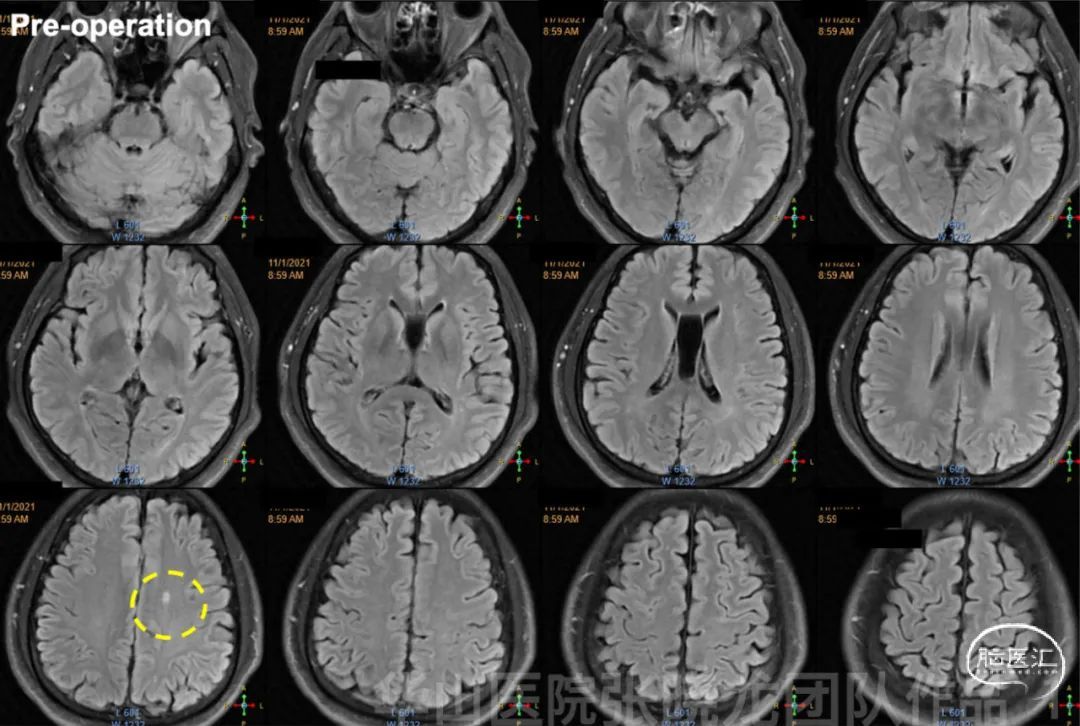

图 1. 术前当地医院MRI提示左侧顶叶点状梗死灶。

图 2. 高分辨率磁共振提示基底动脉瘤壁明显强化,左侧大脑中动脉瘤壁及M1段血管壁轻度强化。